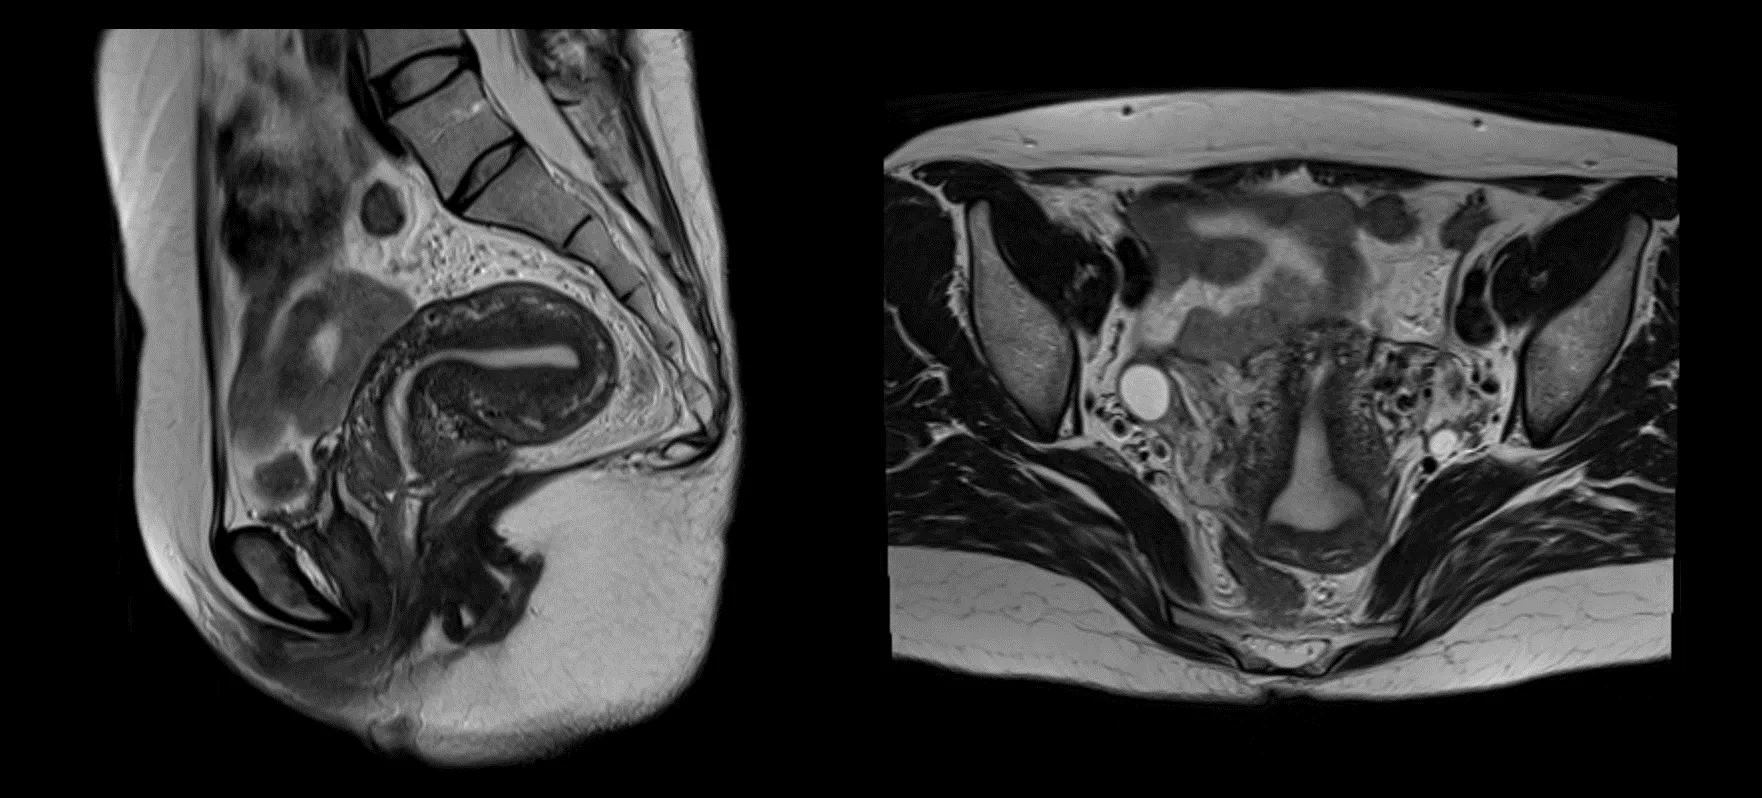

明確な診断を下すためにいくつかの検査を要求する場合があります。画像検査は、腹膜内の異常な塊や肉芽を探すのに役立ちます。これらのテストには次のものが含まれます。

• MRI スキャン: MRI スキャンは、小さな腹膜癌腫症の検出において CT スキャンよりも感度が高くなります。これらは、状態を診断し、病期分類するために選択されるモダリティです。

MRI スキャンを受ける場合もあります。 MRI では、粘液性卵巣がんが原発腫瘍なのか、それとも体内の別の部位から転移しているのかを確認できます。